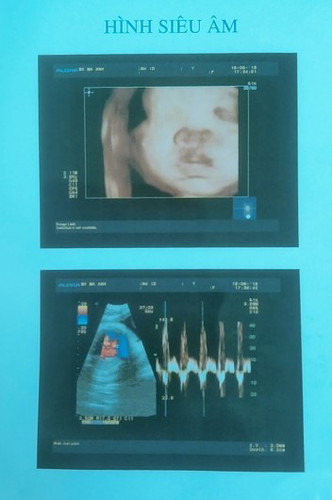

Thường bé xoay đầu thì bao lâu mới sinh vậy các mom.. nay ku được 32w. Đc 2050 gam rồi cô chú ơi 😍